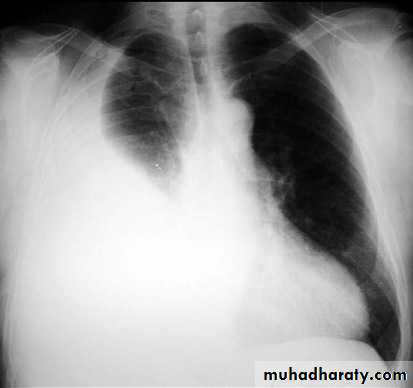

Pleural effusion

50.pleural effusion

51.pleural effusion .